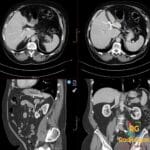

- Radiology Cases: Images with a to-the-point discussion highlighting the specific diagnostic criteria.

- Radiology Case of the Day Collection: Aunt-Minnie Board Cases for Rapid Review.

- Radiology Spotters: 700+ spot / “Aunt-Minnie” cases divided into sets of 10 each!